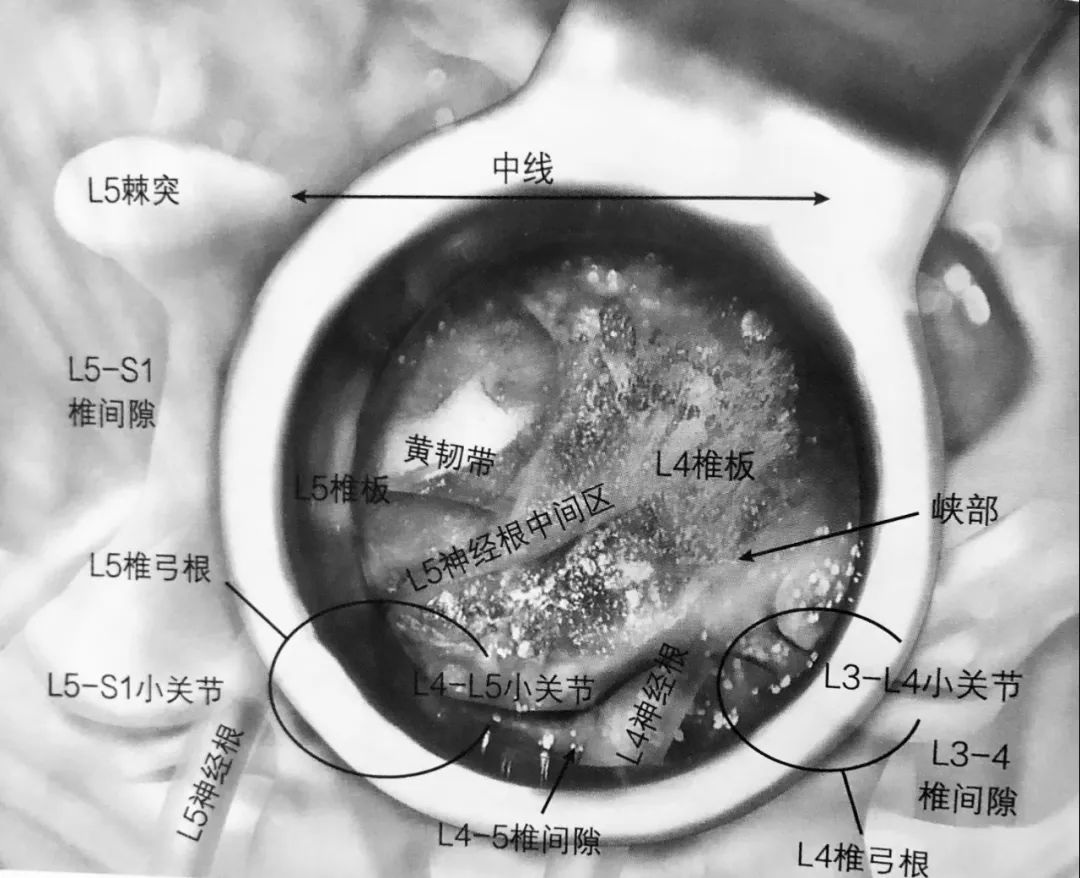

1. 术前准备要点:

2. 把工作通道准确放置在病变水平,完成最初的显露。通常情况下要去除椎板上附着的残余椎旁肌肉组织。

3. 一旦显露椎板,用高速磨钻磨除椎板,仅剩下黄韧带。椎板切除术要通过峡部延伸至外侧。取下的骨植入专门的收集袋中保存。

4. 椎板切除术向头端延至黄韧带止点,硬膜外脂肪或硬膜囊通常能看到。如图,椎板切除术切除范围的头端标志,磨钻用来切除外侧的峡部。

5. 一旦磨钻通过峡部,下关节突就可以去除,完成小关节切除术,显露病变椎间隙。

6. 切除黄韧带。最开始的时候要保留黄韧带,在实施减压时能起到保护硬膜囊的作用。

7. 应用双极电凝凝结椎间隙静脉丛止血。

8. 一旦完成静脉丛电凝止血,下位的椎弓根(L5)及 L4-5 椎间隙就能看得很清楚。L5 神经根中间部就在椎弓根内缘。L4 神经根出口就在椎间隙上缘,但并不一定需要显露。

9. 经椎间孔椎间融合术(TLIF)操作空间在椎间孔上位神经根出口的内侧。准备椎间植骨需要在侧位透视下进行。

10. 联合应用桨状撑开器及终板刮刀清理椎间组织,以利后期植骨。

11. 一旦椎间盘组织清理干净、终板准备完毕后,把一漏斗置于相应椎间隙。把椎板切除过程中收集的骨碎片植入椎间隙。

12. 植入椎间融合器,注意保护好神经根。

13. 椎间融合器要倾斜于中线植入椎间隙。如果要对对侧进行减压,可以调整工作通道倾斜指向靠近硬膜囊侧。

14. 潜在风险:不完全的小关节切除会妨碍椎间隙的显露,使得经椎间孔通道变得很狭窄,随后可能会被迫植入不够大的椎间融合器,从而使椎间融合器移位及假关节形成的发生率增高。